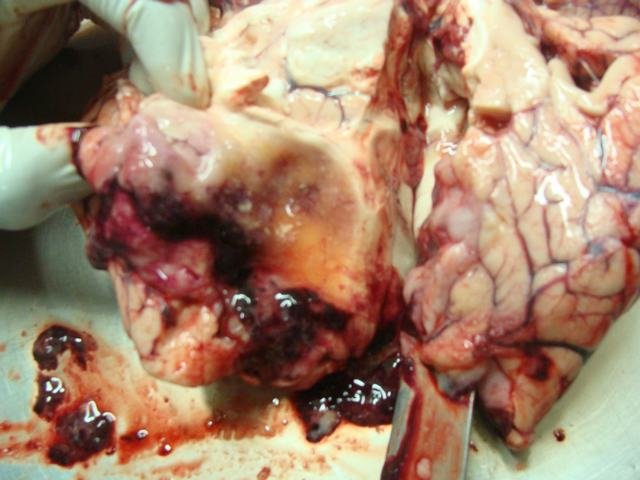

cerebral cyst